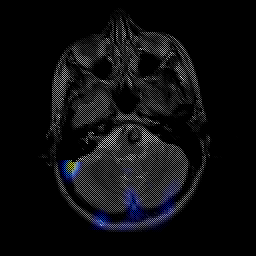

overlay -- Slice #5

[Home][Help][Clinical] Slice 5